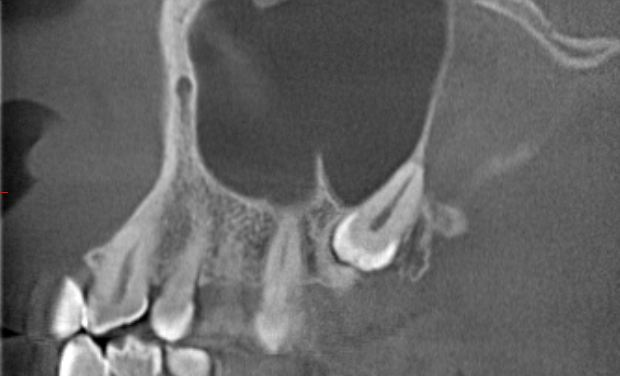

(可以通过CBCT观察牙齿与颌骨、下牙槽神经管、上颌窦的位置关系)